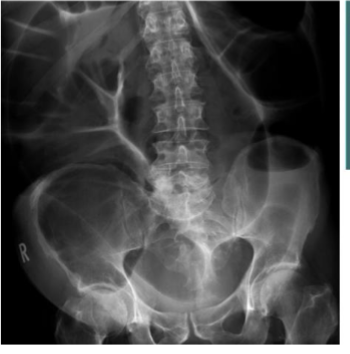

What is this

Large bowel obstruction